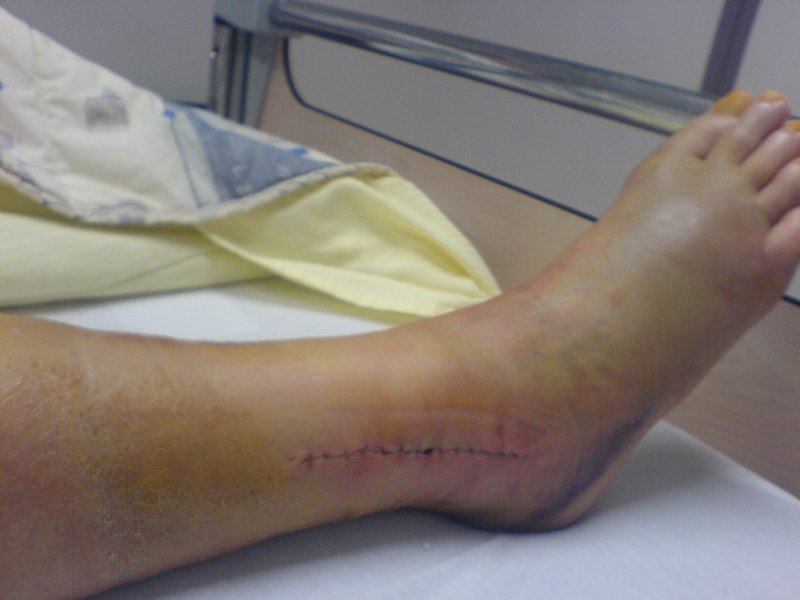

My ankle isn’t sore any more but it was, watch next…

Whooooooo Buddy!!! Owwwwwwww… did you do that unicycling?

Awesome pix.

I am glad that your recovery was strong.

Those pics make me shudder! :frowning:

Yes, he did that will unicycling.

AND it was during a shoot for national Dutch TV, so everybody saw it.